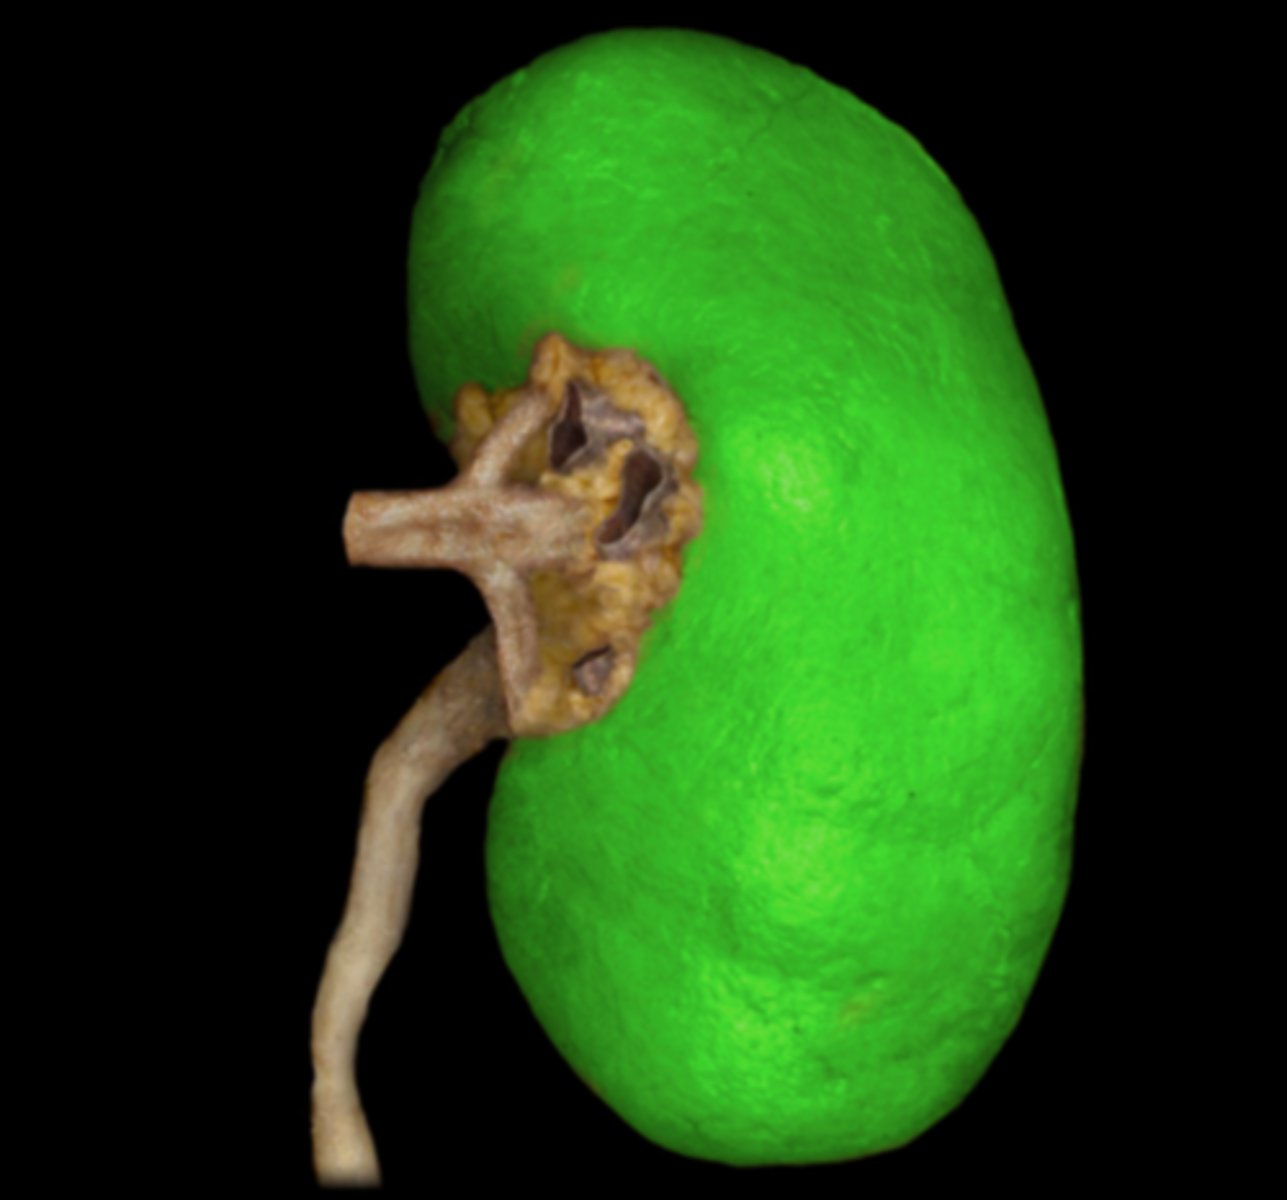

Right Kidney

Left Kidney

Renal Capsule

Renal Pelvis

Renal Hilum

Right Ureter

Left Ureter